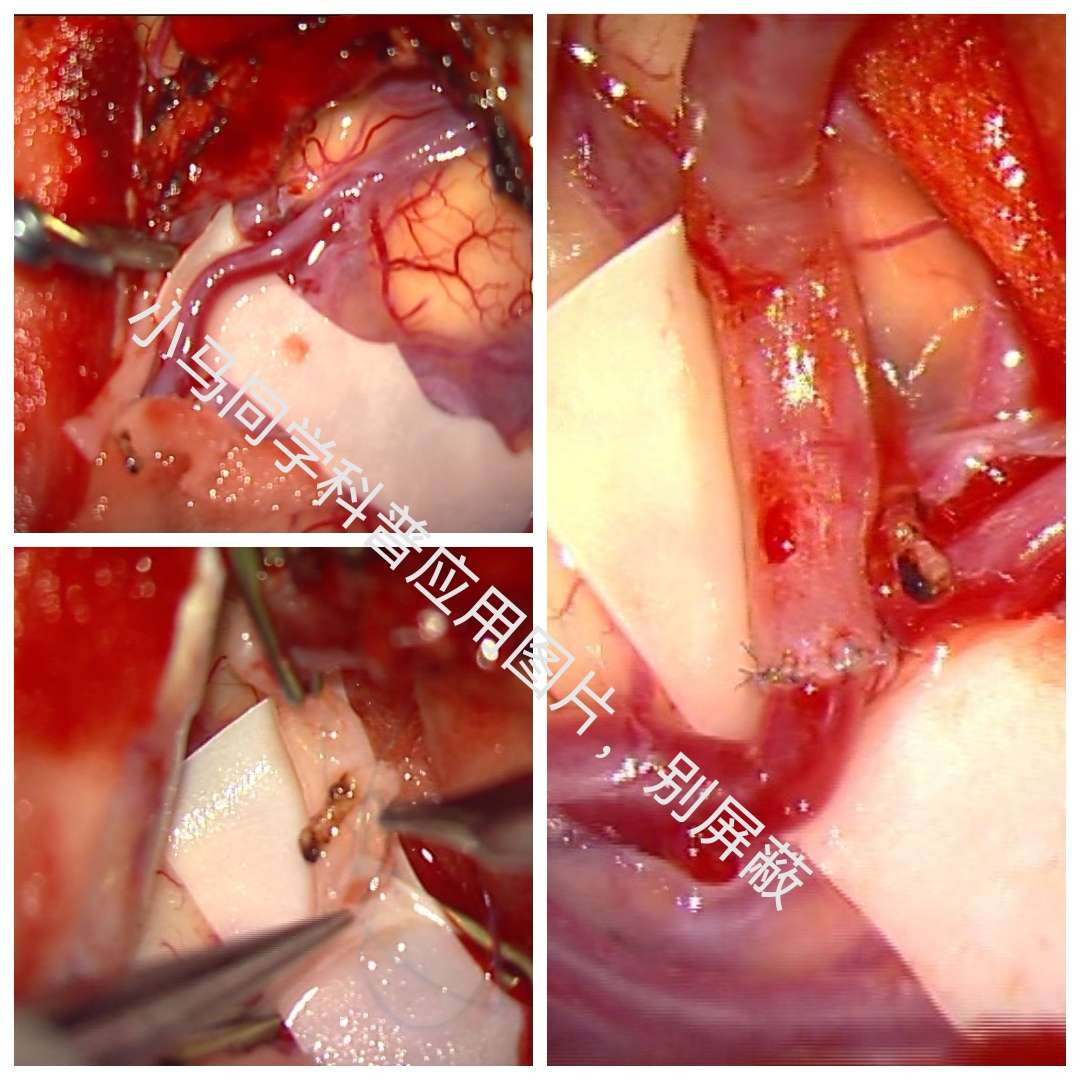

术中游离颞浅动脉,暴露大脑中动脉M4段,行STA-MCA吻合术。

半年后患者来我科复查DSA。颞浅动脉与M4血管吻合满意,颈外动脉造影可见大脑中动脉显影,天堑造通途。。。